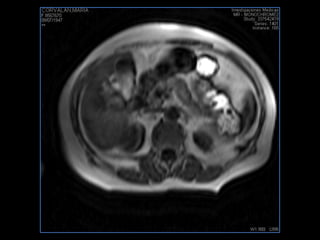

PROTOCOLO pancreas/ riñon AXIAL fat sat /AX in phase out phase AX T1 +SAG T2  COR T2, CON   GADOLINIO :  COR T1+AX T1(DIN) SAT: NO  FASE: RL THK: 4MM  COIL:  GAP: (FACTOR 1.4) 1MM FOV: 40 CM NEX:2 SINCRONIZACION RESPIRATORIA EN 3 O 4 CICLOS ALE